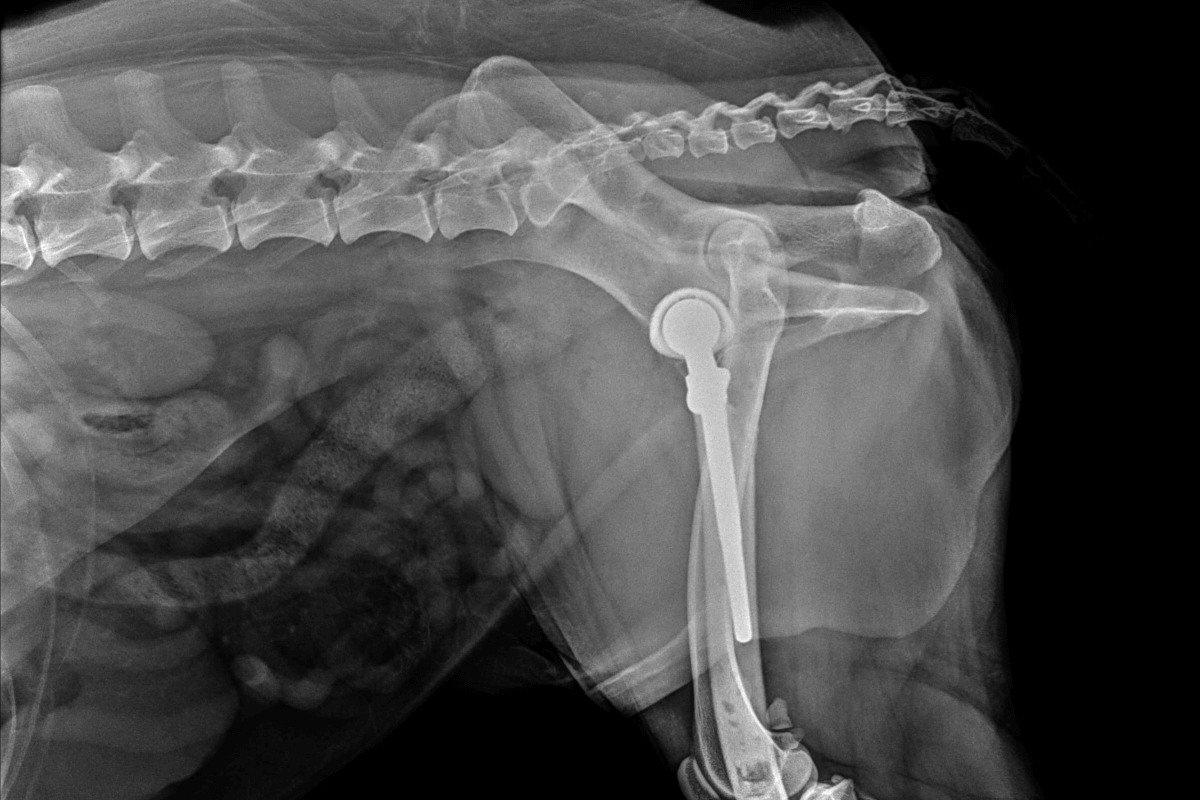

Tras optimizar el peso del paciente, un aspecto crucial en estos casos, se decidió realizar la implantación de una prótesis total de cadera híbrida. Se trata de una técnica utilizada en medicina veterinaria de alto nivel que consiste en sustituir completamente la articulación dañada por componentes artificiales diseñados para devolver la funcionalidad, eliminar el dolor y permitir una vida activa y sin limitaciones.

"Las alternativas conservadoras se descartaron por el elevado riesgo de fracaso funcional, dado el grado de degeneración de la articulación. En estos casos, la prótesis es el tratamiento de elección, porque permite restaurar completamente la funcionalidad y neutralizar el dolor a largo plazo", explica Juan García. Se implantaron componentes adaptados específicamente a la morfología del paciente: copa acetabular de 24 mm, vástago femoral #6 y cabeza protésica de +6 mm.